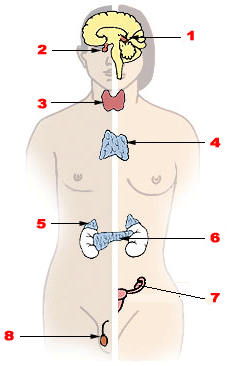

Las glándulas endocrinas no poseen ductos por donde secretar los productos que sintetizan en su interior, por lo que sus productos secretorios se vierten directamente al torrente sanguíneo o hacia el interior de los vasos linfáticos, según sea el caso.

Estas glándulas se encargan principalmente de la liberación de hormonas, las cuales son distribuidas hacia los distintos órganos “diana”. Las glándulas endocrinas más importantes del cuerpo son las glándulas suprarrenales o adrenales, la hipófisis, la tiroides, la paratiroides y la glándula pineal, los ovarios, la placenta y los testículos.

– Las glándulas suprarrenales se encuentran en el polo superior de los riñones y producen hormonas esteroideas y catecolaminas.

– La hipófisis se encarga de producir y secretar diferentes hormonas que participan de la regulación del crecimiento, la reproducción y el metabolismo.

– La tiroides se encuentra en el cuello y participa de la secreción de la hormona tiroxina, triyodotironina y calcitonina, que también influyen sobre el metabolismo.

– La glándula pineal es controlada por los períodos de luz y oscuridad y diversas líneas de evidencia sugieren que influyen sobre la actividad y la función de las gónadas.

– Los ovarios, la placenta y los testículos se encargan de la secreción de hormonas “sexuales” que influyen sobre el desarrollo de los órganos sexuales y por ende, sobre la definición del sexo y la reproducción.

Entre las hormonas secretadas por las glándulas endocrinas están péptidos y proteínas, aminoácidos modificados, esteroides y glucoproteínas.

La característica principal de las glándulas endocrinas es que sus células están organizadas en forma de “cordones” o folículos.